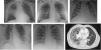

ResultsFive patients with PCR confirmed COVID19 or clinical and radiological suspicion were diagnosed of pneumococcal infection. In all cases chest X-ray were abnormal, with unilateral or bilateral infiltrates. Procalcitonin showed to be not sensitive enough to detect pneumococcal infection. Antibiotherapy was promptly started in all five cases with subsequent satisfactory evolution.

ConclusionInternational guidelines do not include the universal screening for bacterial co-infection. Radiological pattern of COVID-19 can be indistinguishable from that of pneumococcus pneumonia and frequency of co-infection is not well stablished, therefore clinicians should be aware of the possible SARS-CoV-2-pneumococcus association to avoid misdiagnosis and delay antibiotic therapy.